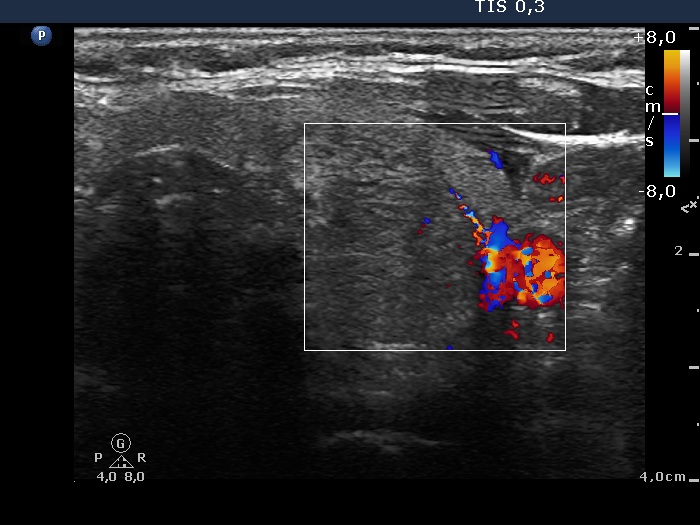

Left lobe, transverse scan, color Doppler method. The nodule shows signs of perinodular blood flow.